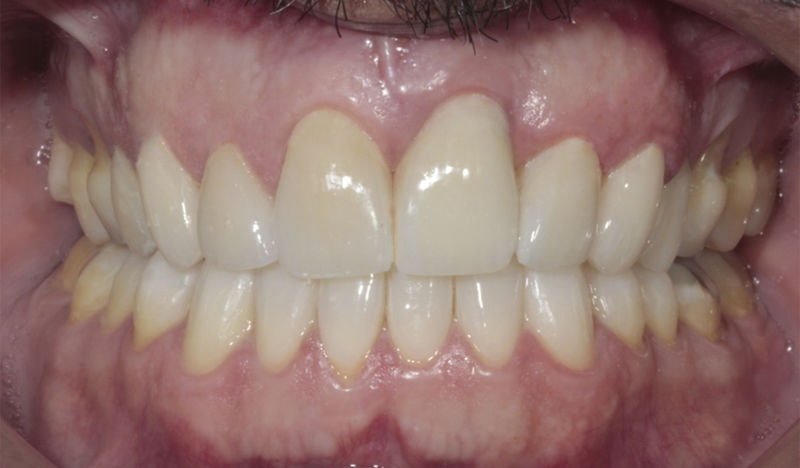

Implantes, ortodoncia y coronas.